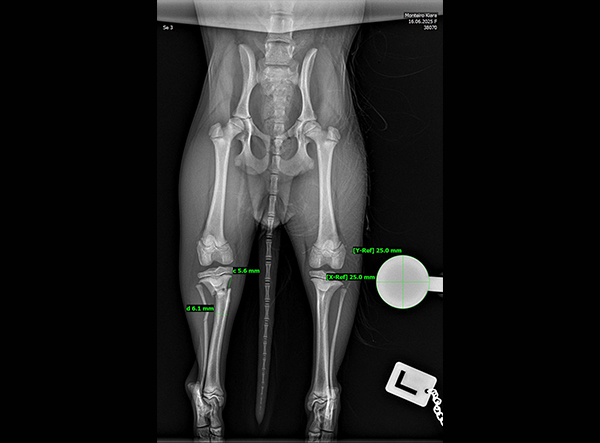

The patient, an 18-week-old female Yorkshire Terrier, was referred for surgery on October 21, 2025. The dog had sustained a fall from the owner’s arms, resulting in a fracture of the proximal tibial metaphysis just below the growth plate, along with a fibular fracture. Given the patient’s very small size and young age, precise anatomical fixation and minimal disruption of the growth zone were essential.

The surgery was completed without complications. Postoperative radiographs confirmed anatomical alignment and stable fixation. With careful rehabilitation, the young Yorkshire Terrier is expected to regain full function and resume normal activity pain-free.